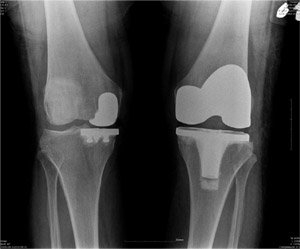

무릎관절(슬관절) 수술은 크게 손상된 연골부위가 너무 커 모두를 인공관절로 대체하는 슬관절 전치환술, 체중이 부하되는 무릎 안쪽과 같은 한쪽의 연골이 마모된 곳을 선택적으로 수술하는 슬관절 부분치환술로 나누어 볼 수 있다. 부분치환술의 특징은 관절의 건강한 부분을 보존함으로써 본래의 자기 관절의 기능을 최대한 보존할 수 있다는데 있다. 이렇게 함으로써 정상 관절의 역할을 보존하여 관절 운동의 각도도 좋아지기 때문에 무릎을 구부리는 것이 쉬우며 방바닥에 앉거나 쪼그리고 앉을 수 있을 정도로 가동성이 좋다. 그뿐만 아니라 인대를 비롯한 자기관절의 구조를 최대한 보존함으로써 위치 감각도 유지할 수 있기 때문에 계단 오르내리기도 더 쉬워지게 된다. 연세사랑병원 권오룡 소장은 “부분치환술은 7cm정도의 절개로도 수술이 가능하다.”며, “무릎 관절의 손상되지 않은 부분을 보존할 수 있기 때문에 수술 후 기능 회복은 물론 입원 및 재활기간도 단축시킬 수 있다.”고 말했다.

또한 슬관절 부분치환술은 전치환술보다 피부절개가 짧고 수술 후 출혈이 훨씬 적어 환자의 회복이 빠르며 수술 후의 운동범위의 회복도 좋기 때문에 환자의 만족도가 더 높은 편이다. 물론 슬관절 전치환술에 비해 단점도 있다. 무릎관절의 변형 정도가 심한 환자나 운동범위가 심하게 줄어들어 있는 환자, 비만인 환자, 류마티스 관절염 등의 염증성 관절염이 있는 환자, 전방십자인대 등의 무릎 인대가 좋지 않은 환자에서는 부분치환술을 잘 시행하지 않거나 제한적으로 시행한다. 또한 무릎 각도를 맞추는 등의 정교한 수술을 요하기 때문에 경험이 많은 전문의가 수술을 해야 결과가 좋다.